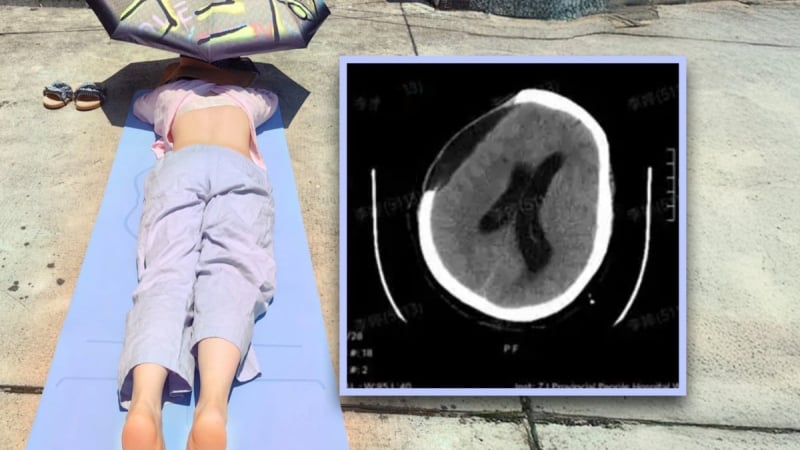

Người phụ nữ cao tuổi “nướng mình” dưới cái nắng gay gắt vì tin theo mẹo y học cổ truyền, đã bị xuất huyết não.

Vụ việc của một phụ nữ 67 tuổi ở tỉnh Chiết Giang, miền đông nam Trung Quốc, bị xuất huyết não và rơi vào hôn mê sau khi nằm tắm nắng trong hai giờ để “chữa bệnh” theo một mẹo dân gian, đang gây chấn động dư luận nước này.

Người phụ nữ họ Vương đã áp dụng một phương pháp truyền miệng trong y học cổ truyền Trung Quốc cho rằng “tắm nắng vùng lưng giúp làm ấm dương khí, xua tan hàn khí và chữa khỏi bệnh tật”. Vào khoảng trưa, bà Vương nằm sấp ngoài trời, ngay trước nhà, trong điều kiện nắng gắt suốt hai tiếng đồng hồ.

Tuy nhiên, ngay sau khi vào nhà, bà bất ngờ ngất xỉu và mất ý thức. Bà nhanh chóng được đưa tới bệnh viện, nơi các bác sĩ xác định bà bị xuất huyết não do phình mạch và tụt não, một tình trạng nguy hiểm đến tính mạng. Ca phẫu thuật khẩn cấp được tiến hành, nhưng bà vẫn rơi vào trạng thái hôn mê.

Ông Diệp Tường Minh, Giám đốc Khoa Phục hồi chức năng tại Bệnh viện Nhân dân tỉnh Chiết Giang cho biết, bà Vương bị tổn thương não nghiêm trọng.

Việc nằm liệt giường kéo dài khiến bà đối mặt với nguy cơ cao mắc các biến chứng khác. Sau đó, bà phải trải qua quá trình phục hồi chức năng kéo dài, bao gồm châm cứu và nhiều ca phẫu thuật. Dần dần, bà đã có thể ngồi dậy, đứng, nói chuyện và tự ăn uống trở lại.

Ông Diệp nhấn mạnh: “Quan niệm tắm nắng chữa bách bệnh hoàn toàn không có cơ sở khoa học. Việc tiếp xúc lâu dài với ánh nắng mặt trời trong điều kiện nhiệt độ cao đặc biệt nguy hiểm đối với người cao tuổi hoặc những người có bệnh lý nền như cao huyết áp, bệnh mạch máu não. Điều này có thể dẫn đến say nắng hoặc đột quỵ”.